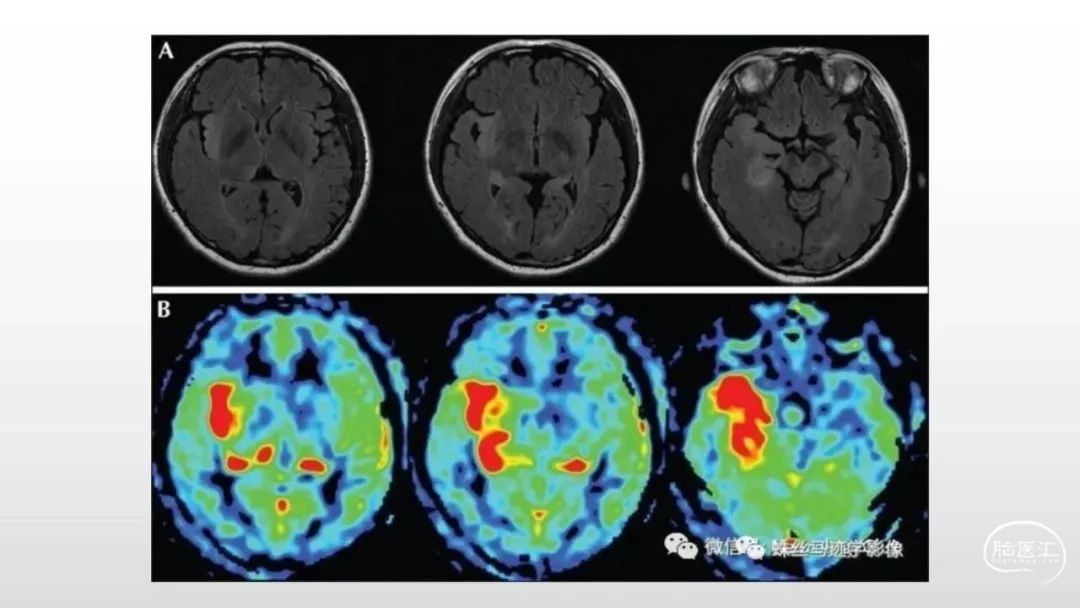

颅脑影像诊断基础知识讲座:感染和免疫性疾病2